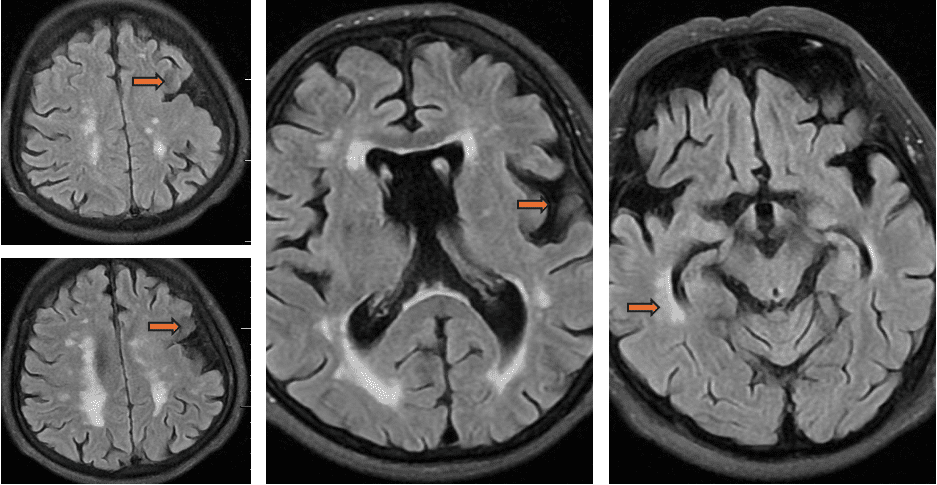

头MRI(2024-4-30 Flair序列):左上下图提示左侧额叶组织结构异常,考虑灰质异位;中图可见双侧侧脑室周围可见缺血脱髓鞘改变;双侧外侧裂、额叶皮层萎缩明显;右图可见双侧海马外侧边缘稍高信号影。